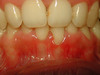

Cas 3